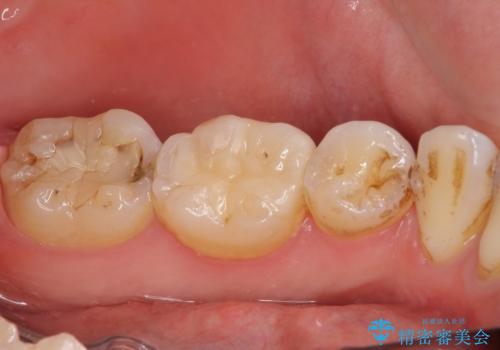

- 下の奥歯に虫歯ができてしまったとのことで来院された患者様です。

他にも気になる歯はありましたが、急を要する1歯のみをセラミックインレーにて修復治療を行うこととしました。

奥歯において、隣の歯と接触する部分に虫歯が及んでしまった場合、その場で充填を行う処置(コンポジットレジン修復)ですと、充填の縁に大きなギャップが生じてしまう可能性が高く、2次的な虫歯を引き起こすことになります。

また、処置した歯の後方にある歯は保険診療で使用するレジンインレーが装着されていますが、縁に虫歯が出来はじめていることが分かります。

再治療が必要とならないようにするにはどうしたらよいか、担当医とよく相談されると良いと思います。